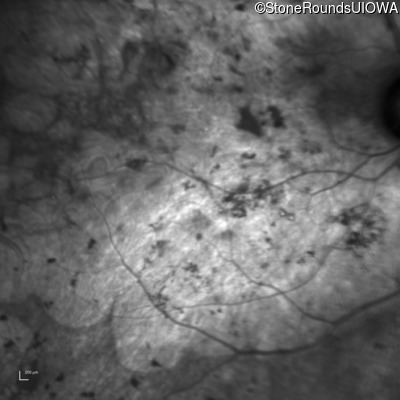

Visit at age: 61 years

Fundus Photography - Right - Light Perception

Exemplar

Fundus Photography - Left - Light Perception

Fundus Montage - Right - Light Perception

Fundus Montage - Left - Light Perception